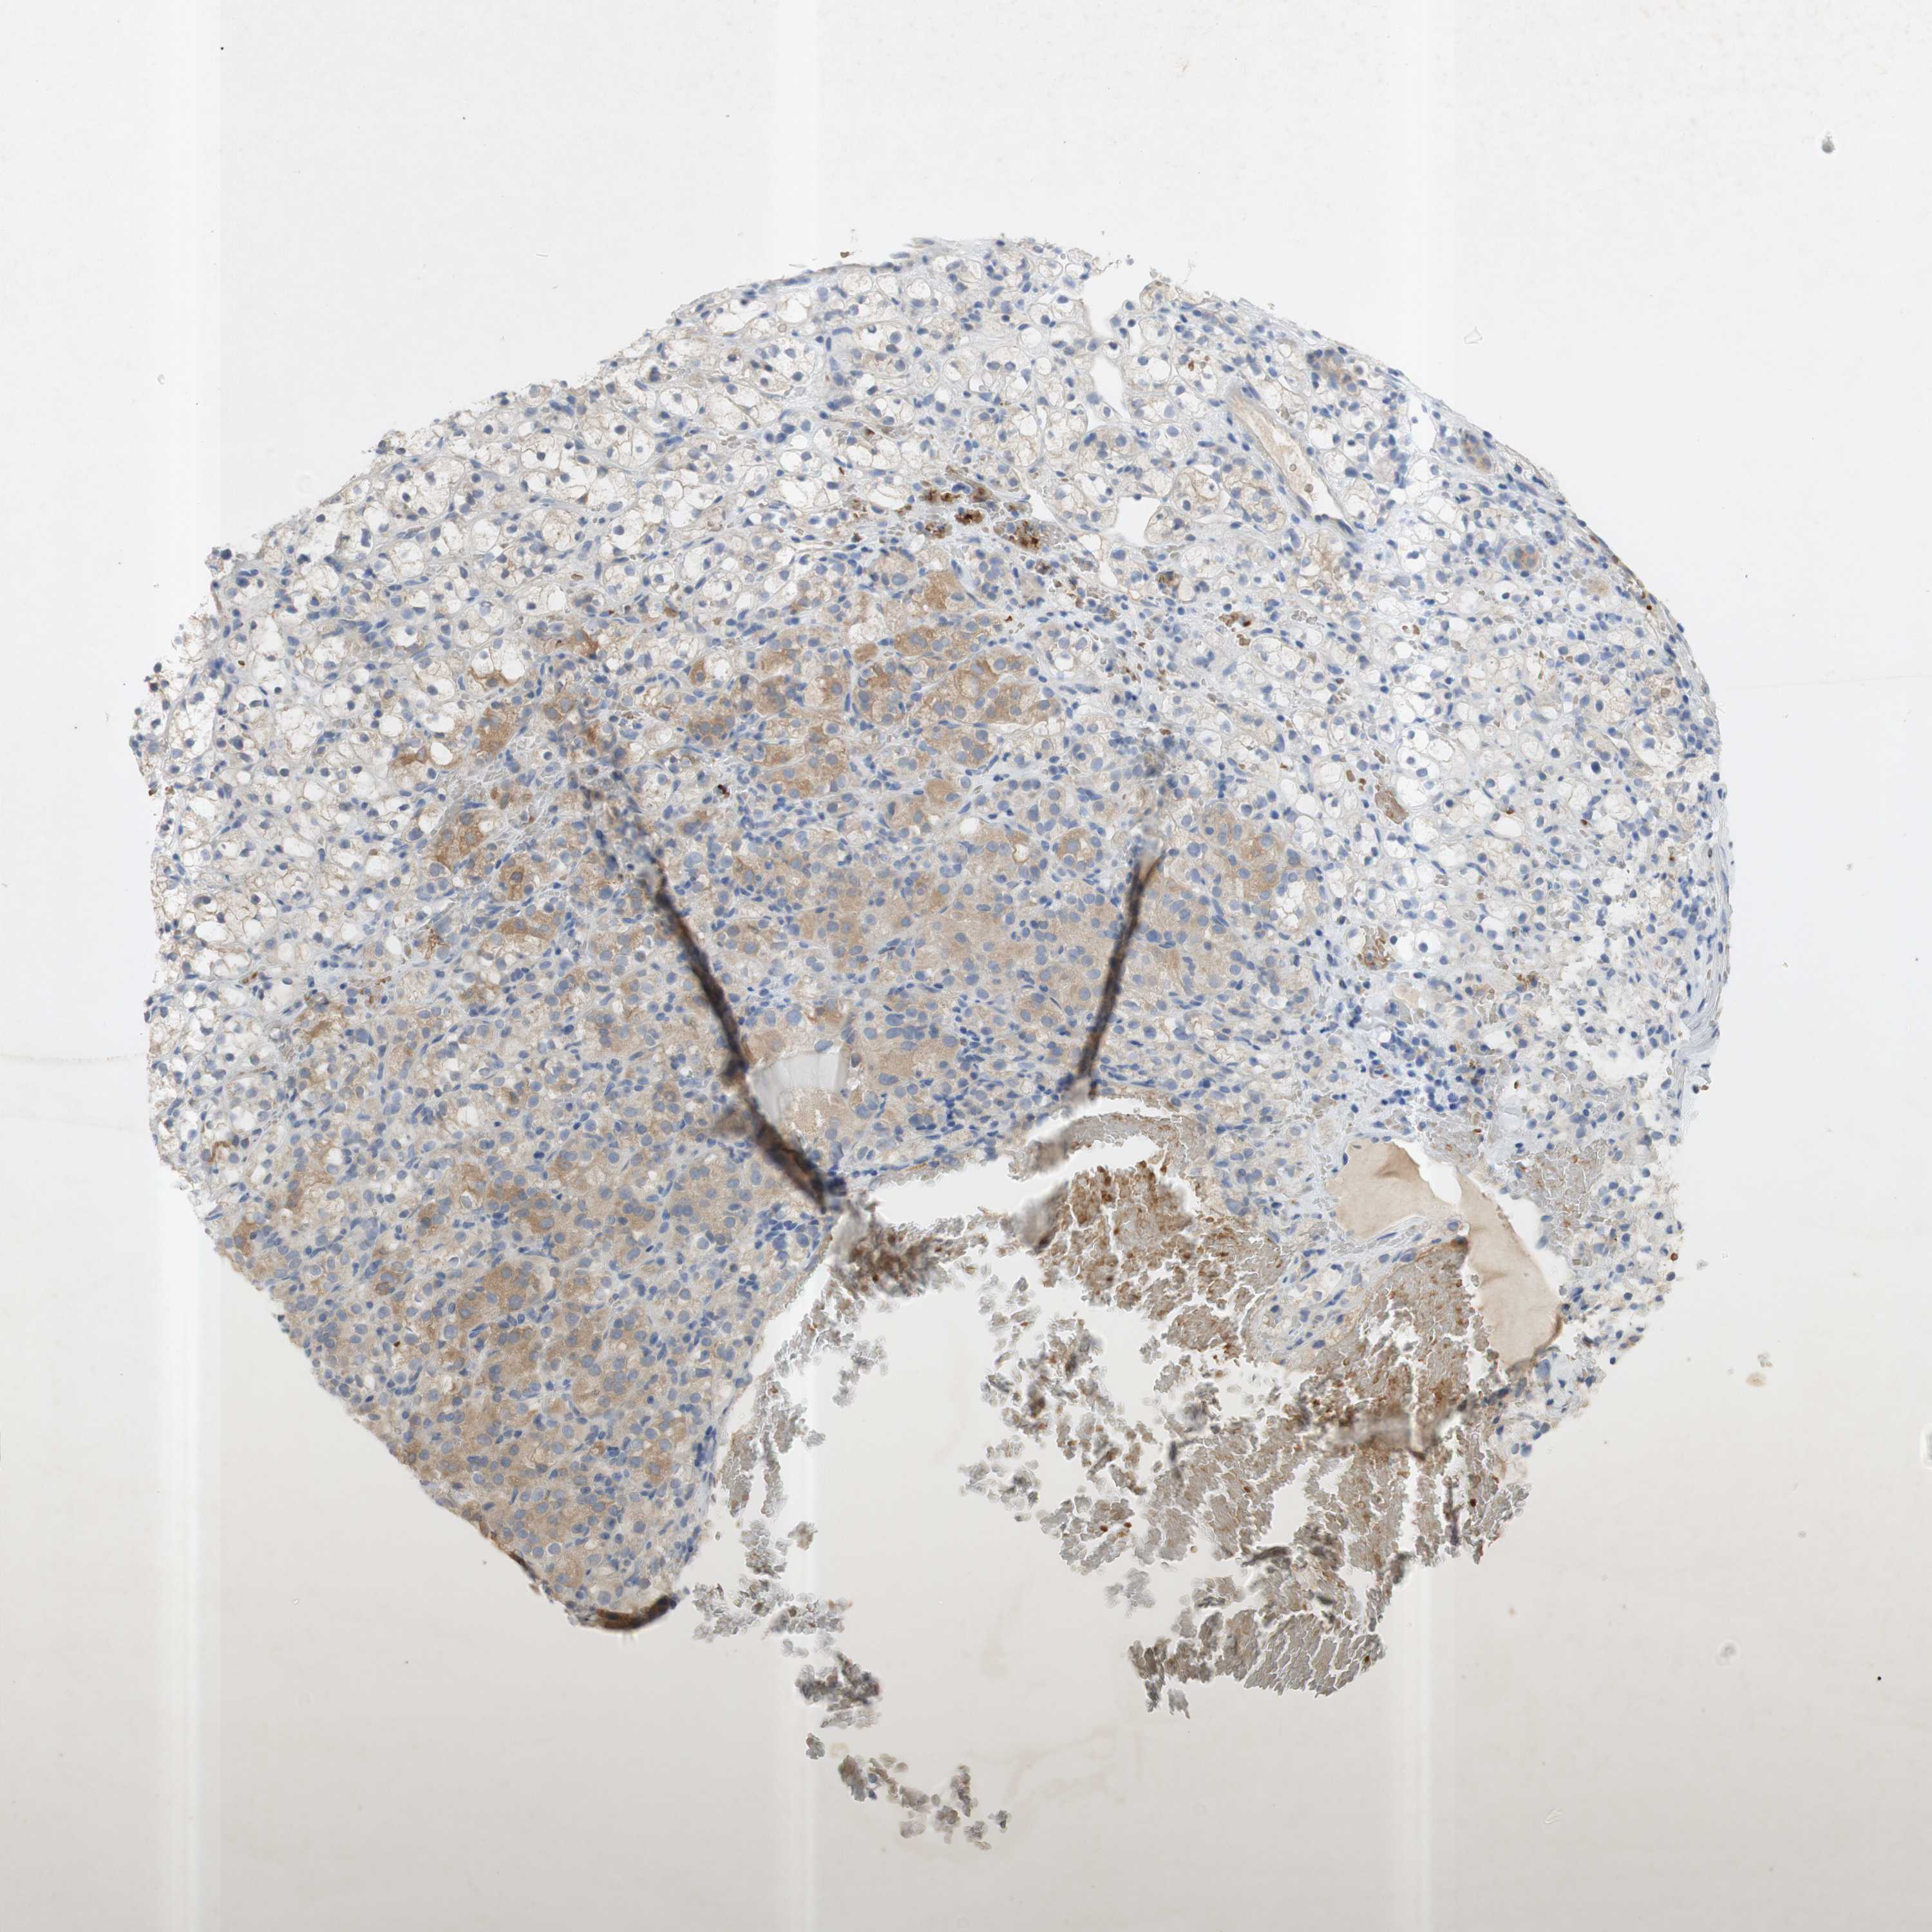

KIDNEY RENAL CLEAR CELL CARCINOMA (VALIDATION) - Interactive survival scatter ploti

The Survival Scatter plot shows the clinical status (i.e. dead or alive) for all individuals in the patient cohort, based on the same data that underlies the corresponding Kaplan-Meier plots. Patients that are alive at last time for follow-up are shown in blue and patients who have died during the study are shown in red.

The x-axis shows the expression levels (FPKM) of the investigated gene in the tumor tissue at the time of diagnosis. The y-axis shows the follow-up time after diagnosis (years). Both axes are complimented with kernel density curves demonstrating the data density over the axes. The top density plot shows the expression levels (FPKM) distribution among dead (red) and alive patients (blue). The right density plot shows the data density of the survived years of dead patients with high and low expression levels respectively, stratified using the cutoff indicated by the vertical dashed line through the Survival Scatter plot. This cutoff is automatically defined based on the FPKM cutoff that minimizes the p-score. The cutoff can be changed by dragging the vertical line or by entering a cutoff value in the square labeled "Current cut-off".

Under the Survival Scatter plot the p-score landscape (black curve; left axis) is shown together with dead median separation (red curve; right axis). Dead median separation is the difference in median mRNA expression between patients who have died with high and low expression, respectively. It is calculated as follows: median FPKM expression of dead patients with high expression - median FPKM expression of dead patients with low expression. This is intended to aid the user in visually exploring custom cutoffs and the associated p-scores and dead median separation.

Individual patient data is displayed and can be filtered by clicking on one or more of the category buttons on the top of the page. Categories describing expression level and patient information include: high, low, alive, dead, female, male and tumor stages. The scale of the x-axis can be toggled between linear and log-scale by clicking on the "x log" button. Mouse-over function shows TCGA ID, patient information and mRNA expression (FPKM) for each patient.

& Survival analysisi

Kaplan-Meier plots summarize results from analysis of correlation between mRNA expression level and patient survival. Patients were divided based on level of expression into one of the two groups "low" (under cut off) or "high" (over cut off). X-axis shows time for survival (years) and y-axis shows the probability of survival, where 1.0 corresponds to 100 percent.

EPO is not prognostic in Kidney Renal Clear Cell Carcinoma (validation)

: 1.85

Average pTPM 7.3

Number of samples 100